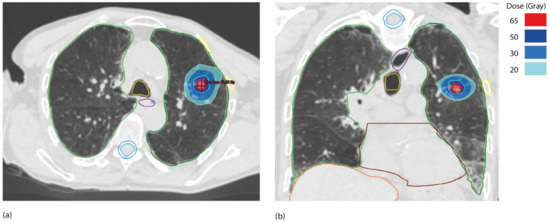

Before treatment can be administered, the location of the tumor or target volume must be confirmed, and immobilization devices must be used to keep the patient precisely in the same position throughout the treatment delivery [4,5]. Extracranial SBRT necessitates the use of appropriate RT devices that allow for a tight gradient of dose and a rapid decrease in dose to maximize healthy tissue organ sparing in order to guarantee maximum normal tissue spearing [6,7] (Figure 1).

We concentrated on the new classification of de novo, oligometastatic, oligorecurrence, and oligoprogressive disease in order to better define the strategies in the various disease settings [2,3]. Figure 2 depicts the most common types of oligometastatic disease treated with SBRT and usual doses and fractionations (Tables 1–4, Figure 2).